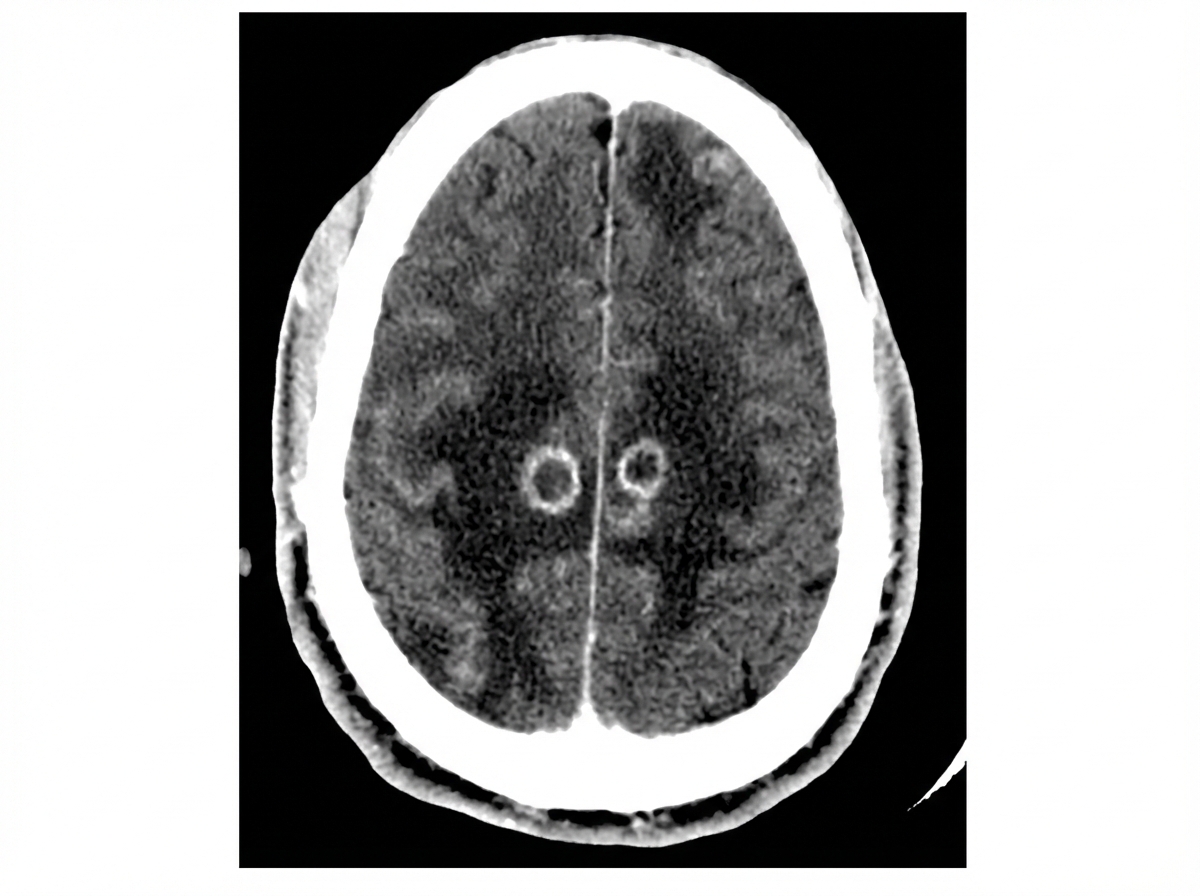

A 32-year-old HIV positive female known to be non-adherent to her treatment regimen, presents to the hospital with the complaint of new-onset headaches. Her vital signs are only significant for a low-grade fever. Neurological examination reveals right-sided upper motor neuron signs, as well as inattention and difficulty with concentration. The patient currently does not have a primary medical provider. A CT of the patients head is shown in the image below. What is the next best step in management for this patient?